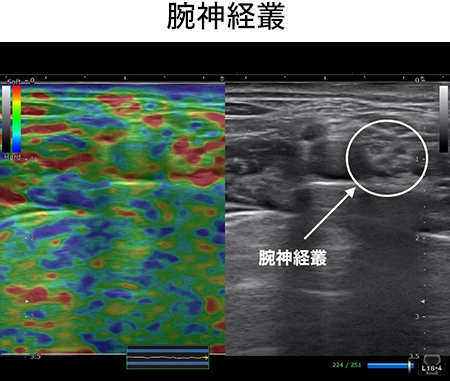

このセッションでは、血管・靭帯・神経をあなたの臨床に取り入れやすくするために筋膜との関係性を明らかにします。例えば腕神経叢は斜角筋と繋がりがありますし、坐骨神経は梨状筋との繋がりがあります。この知識さえあれば、どのタイミングで血管や神経を見ればいいのかがわかり。明日からの臨床ですぐに結果を出すことができるでしょう。

なぜ、僕たちがこんなにも疼痛治療の最前線で、結果を出し続けているのか?それは、正確な触診技術にあります。このセッションでは、ほとんどの理学療法士が知らず、学校では決して教えない、僕たちが日々の研究で獲得した、エコー解剖学に基づいた血管・靭帯・神経を確実に触診するための3つのポイントをお伝えします。

あなたは腕神経叢の解剖を詳しく知っていますか?どの位置にあって、どの深さにあって、どんな走行で、どの組織の間を通るか、などすぐに答えることができますか?腕神経叢もエコー解剖で丸裸にしたからこそ可能となったリリーステクニックです。他のどのセミナーであっても学ぶことはできません。このテクニックを学ぶことであなたは、、、